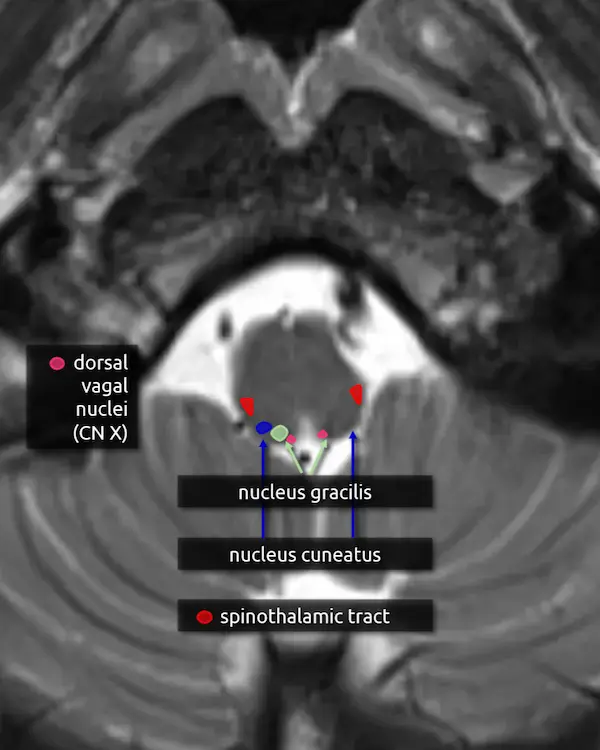

8. Nucleus gracilis and cuneatus

Nucleus gracilis:

a. Located in the medial dorsal mid to lower medulla. It receives sensory input from the lower body (lower trunk, lower limbs) from T7 and below.

Nucleus cuneatus:

a. Located lateral to the nucleus gracilis. It receives sensory input from the upper body (upper trunk, neck, upper limbs) from T6 and above.

First order neurons carrying vibration, fine touch, and proprioception information from the spinal cord synapse with second order neurons in the nucleus gracilis and cuneatus. Second order neuron axons then decussate and travel superiorly through the medial lemniscus before reaching the third order neurons in the ventral posterolateral nucleus (VPL) of the thalamus. Collectively, this is called the dorsal column medial lemniscus (DCML) pathway.

1. Pyramids

2. Pyramidal decussation

3. Nucleus gracilis

4. Nucleus cuneatus